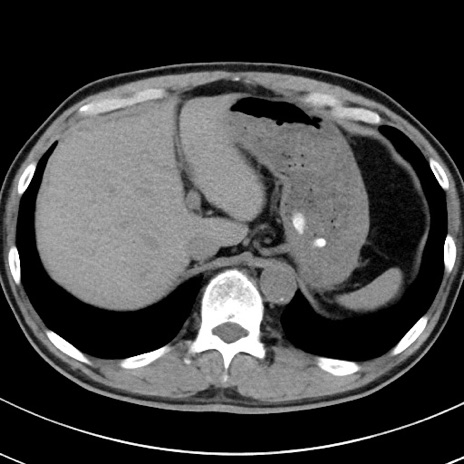

【腹部TIPS】症例29 参考症例 CT(横断像)

症例

70歳代男性